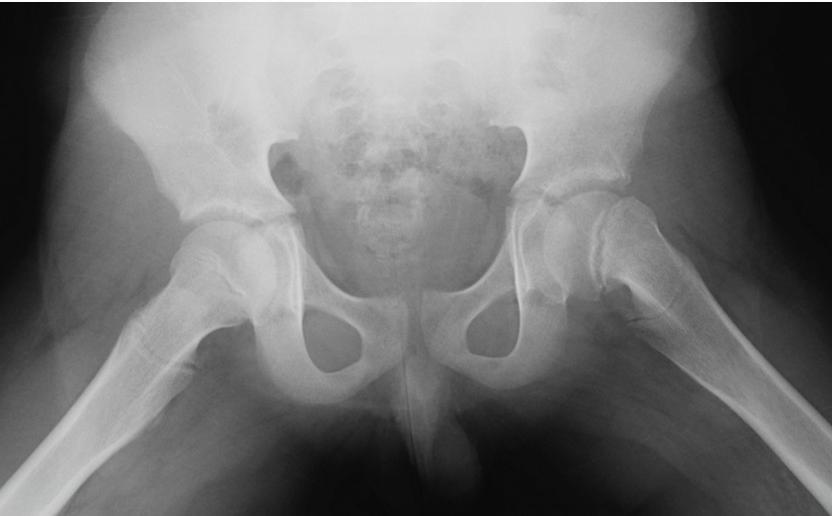

Case 2: 14-year-old boy, limping on left side